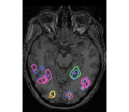

face

vs house

TV-l1

Graph-net

Social sparsity

Finally, an important aspect of the brain decoders is whether they segment well the brain regions that support the decoding. Such a question is hard to validate, yet there is evidence that TV- is a good approach [5]. Fig. 2 displays the decoder maps for the object-recognition tasks. For these tasks, we expect prediction to be driven by the functional areas of the visual cortex [27]. Indeed, the maps outline regions in known visual areas. The graph-net maps are much more scattered and less structured than the others. Conversely, the social sparsity maps are sparser and outline a smaller number of clusters.